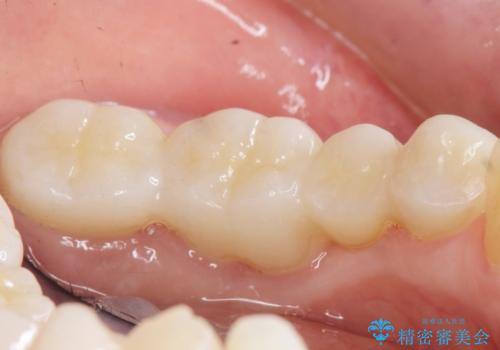

手術後に根管治療を行い、歯肉と骨の治癒を十分に待った後ブリッジによる補綴治療を行いました。

ご希望通り歯を抜かずに残すことができ、喜んで頂けました。

セルフメンテナンスしやすいよう、ブリッジと歯ぐきの間に歯間ブラシを通すことができるように作製しています。

被せ物の種類:オールセラミッククラウン ベレッツァ